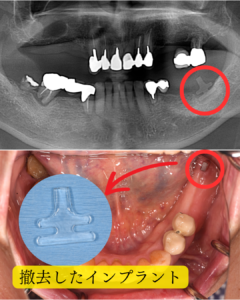

上下共に、奥歯の揺れが大きく、今にも取れそうな状態でした。左下には、20年ほど前に入れた、ブレード型のインプラントが入っていましたが、これも揺れが大きかったため撤去を行っていくことになりました。

インプラント撤去

今では使用されてはいませんが、過去にはこのような板状のブレード型のインプラントが度々使用されていました。インプラント周囲の骨は溶けてしまい、グラグラの状態だったので、撤去を行いました。